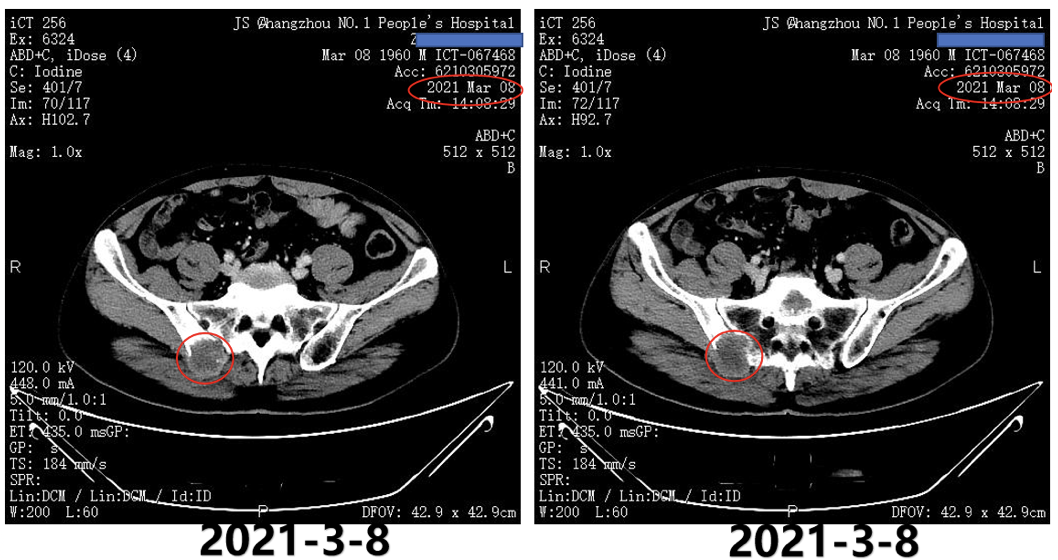

2021年3月8日复查AFP为>1210ng/ml;2021年3月8日复查CT提示,双肺转移双侧肾上腺转移;左侧肾上腺较前变小,但右侧肾上腺明显增大;右侧髂骨转移(图5)。

图5.2021年3月8日复查CT